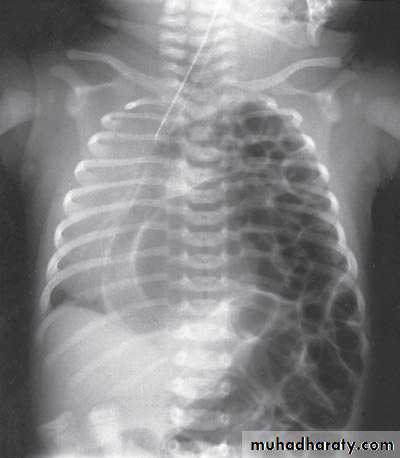

Diaphragmatic eventration